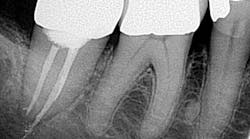

• Access perforations

Drill, poke around. Drill some more. Hmm. I’ve got to be getting close. Let’s just take an x-ray to see how close we are . . . oops! Yeah, that’s happened to me and it’s not how I like to start my root canals (figure 1). The cause of perforations during access is primarily due to lack of attention to the degree of axial inclination and failure to hold the bur parallel to the tooth. (1) Inadequate access can also lead to misdirection and unintended gouging. Signs of perforation include sudden pain, hemorrhaging, burning pain or bad taste during irrigation, periodontal ligament reading from the apex locator, and a radiographically malpositioned file. (1) Prevention includes understanding tooth morphology, accessing without a rubber dam (in instances where angulation, calcified chambers, and misoriented crowns skew tooth alignment), (1) having multiple radiographs to reference, and patience . . . lots and lots of patience, especially when you have small, calcified chambers that want to be eluded.